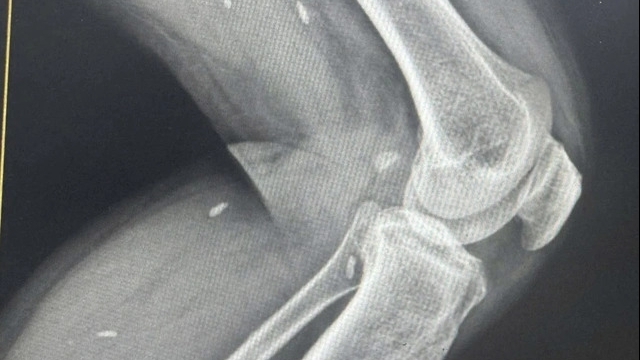

![]() |

| Chụp X – quang kĩ thuật số |